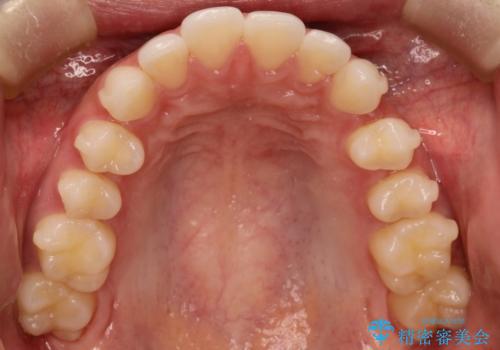

出っ歯の矯正治療 歯を抜かずにインビザラインで

- インビザラインで出っ歯を治したいとの希望がありました。

上顎の歯を全体的に後方に移動させて前歯を引っ込める計画としました。